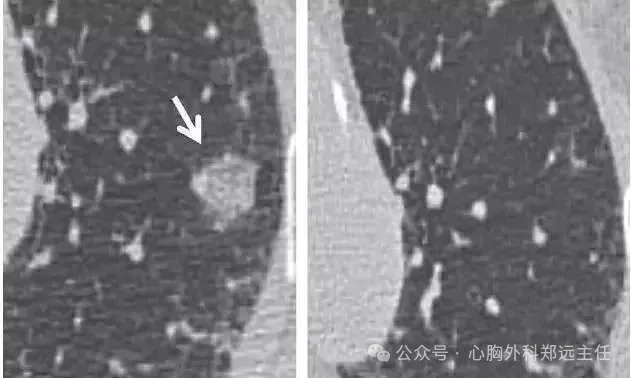

吸入有机粉尘同样也可引发肺结节的形成,例如采棉工人的棉尘肺、吸入谷物粉尘的农民肺以及暴露于木尘的木工等。下图是一位采棉女工,长期吸入植物性粉尘,在肺里形成很多微结节和索条状影。